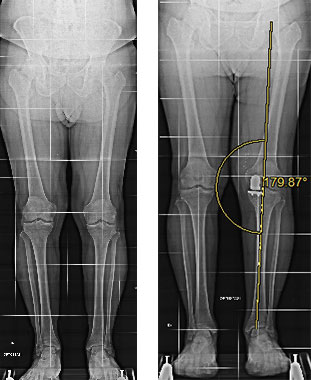

Paziente maschio di 65 anni, affetto da gonartrosi mediale sinistra, trattata con protesi monocompartimentale mediale di ginocchio con tecnica mini invasiva.

Radiografie